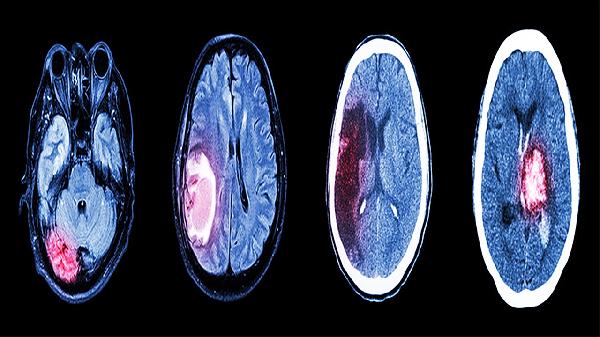

2、CTA检测:CT血管造影能三维重建肾动脉解剖结构,需注射碘对比剂。检查前需评估肾功能,肌酐清除率<30ml/min者慎用。可清晰显示钙化斑块,对支架术后随访具有优势,辐射剂量低于传统DSA造影。

3、MRA检查:磁共振血管成像利用血流信号成像,无需碘对比剂,适合肾功能不全患者。钆对比剂可能引发肾源性系统性纤维化,重度肾衰患者禁用。对纤维肌性发育不良的诊断灵敏度达90%以上。

4、血管造影:数字减影血管造影是诊断金标准,可同时进行介入治疗。需穿刺股动脉并导管置入,存在0.5%的并发症风险。能精确测量狭窄程度和压力梯度,指导血运重建决策。